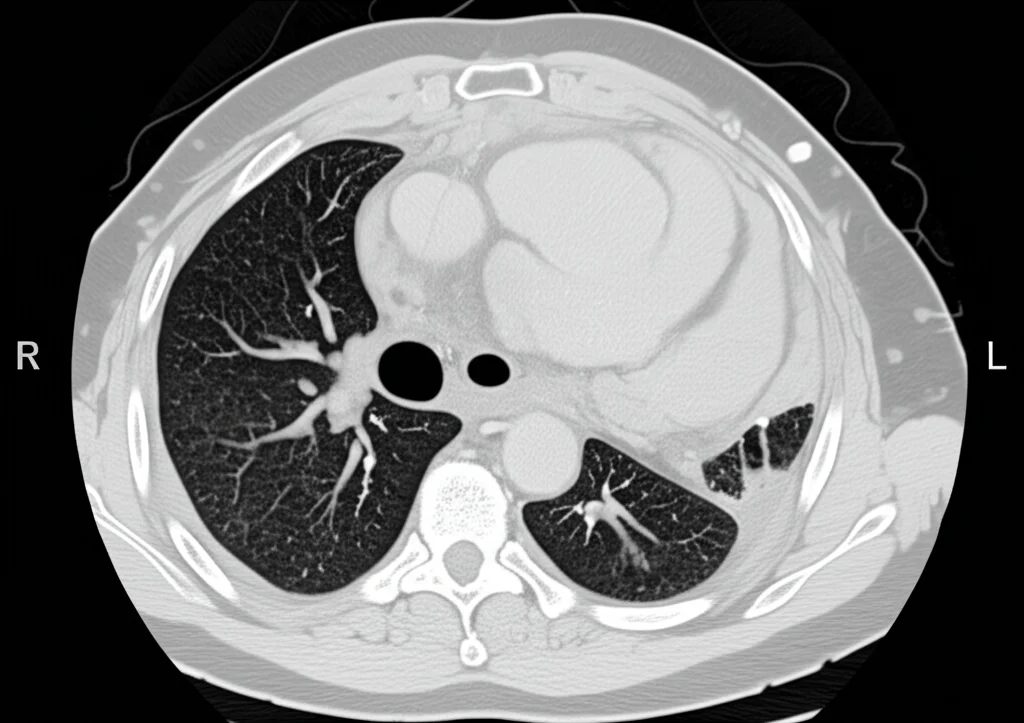

Reperti alla TAC del Torace

La TAC, essendo molto più dettagliata, ha rivelato anomalie in una percentuale maggiore di pazienti (64,4%). Qui i reperti più frequenti includevano:

- Noduli polmonari (26,8%): Piccole opacità rotondeggianti. Spesso sono benigni, ma richiedono attenzione.

- Bronchiectasie (16,9%): Dilatazioni permanenti e irreversibili dei bronchi.

- Atelettasie lineari (13,7%): Piccole aree di collasso polmonare, spesso a forma di striscia.

- Ispessimento delle pareti bronchiali (13,5%): Un segno diretto dell’infiammazione e del rimodellamento delle vie aeree tipico dell’asma.

- Opacità a vetro smerigliato (ground-glass) (12,8%): Aree sfumate che possono indicare infiammazione, infezione o altri processi a livello degli alveoli.